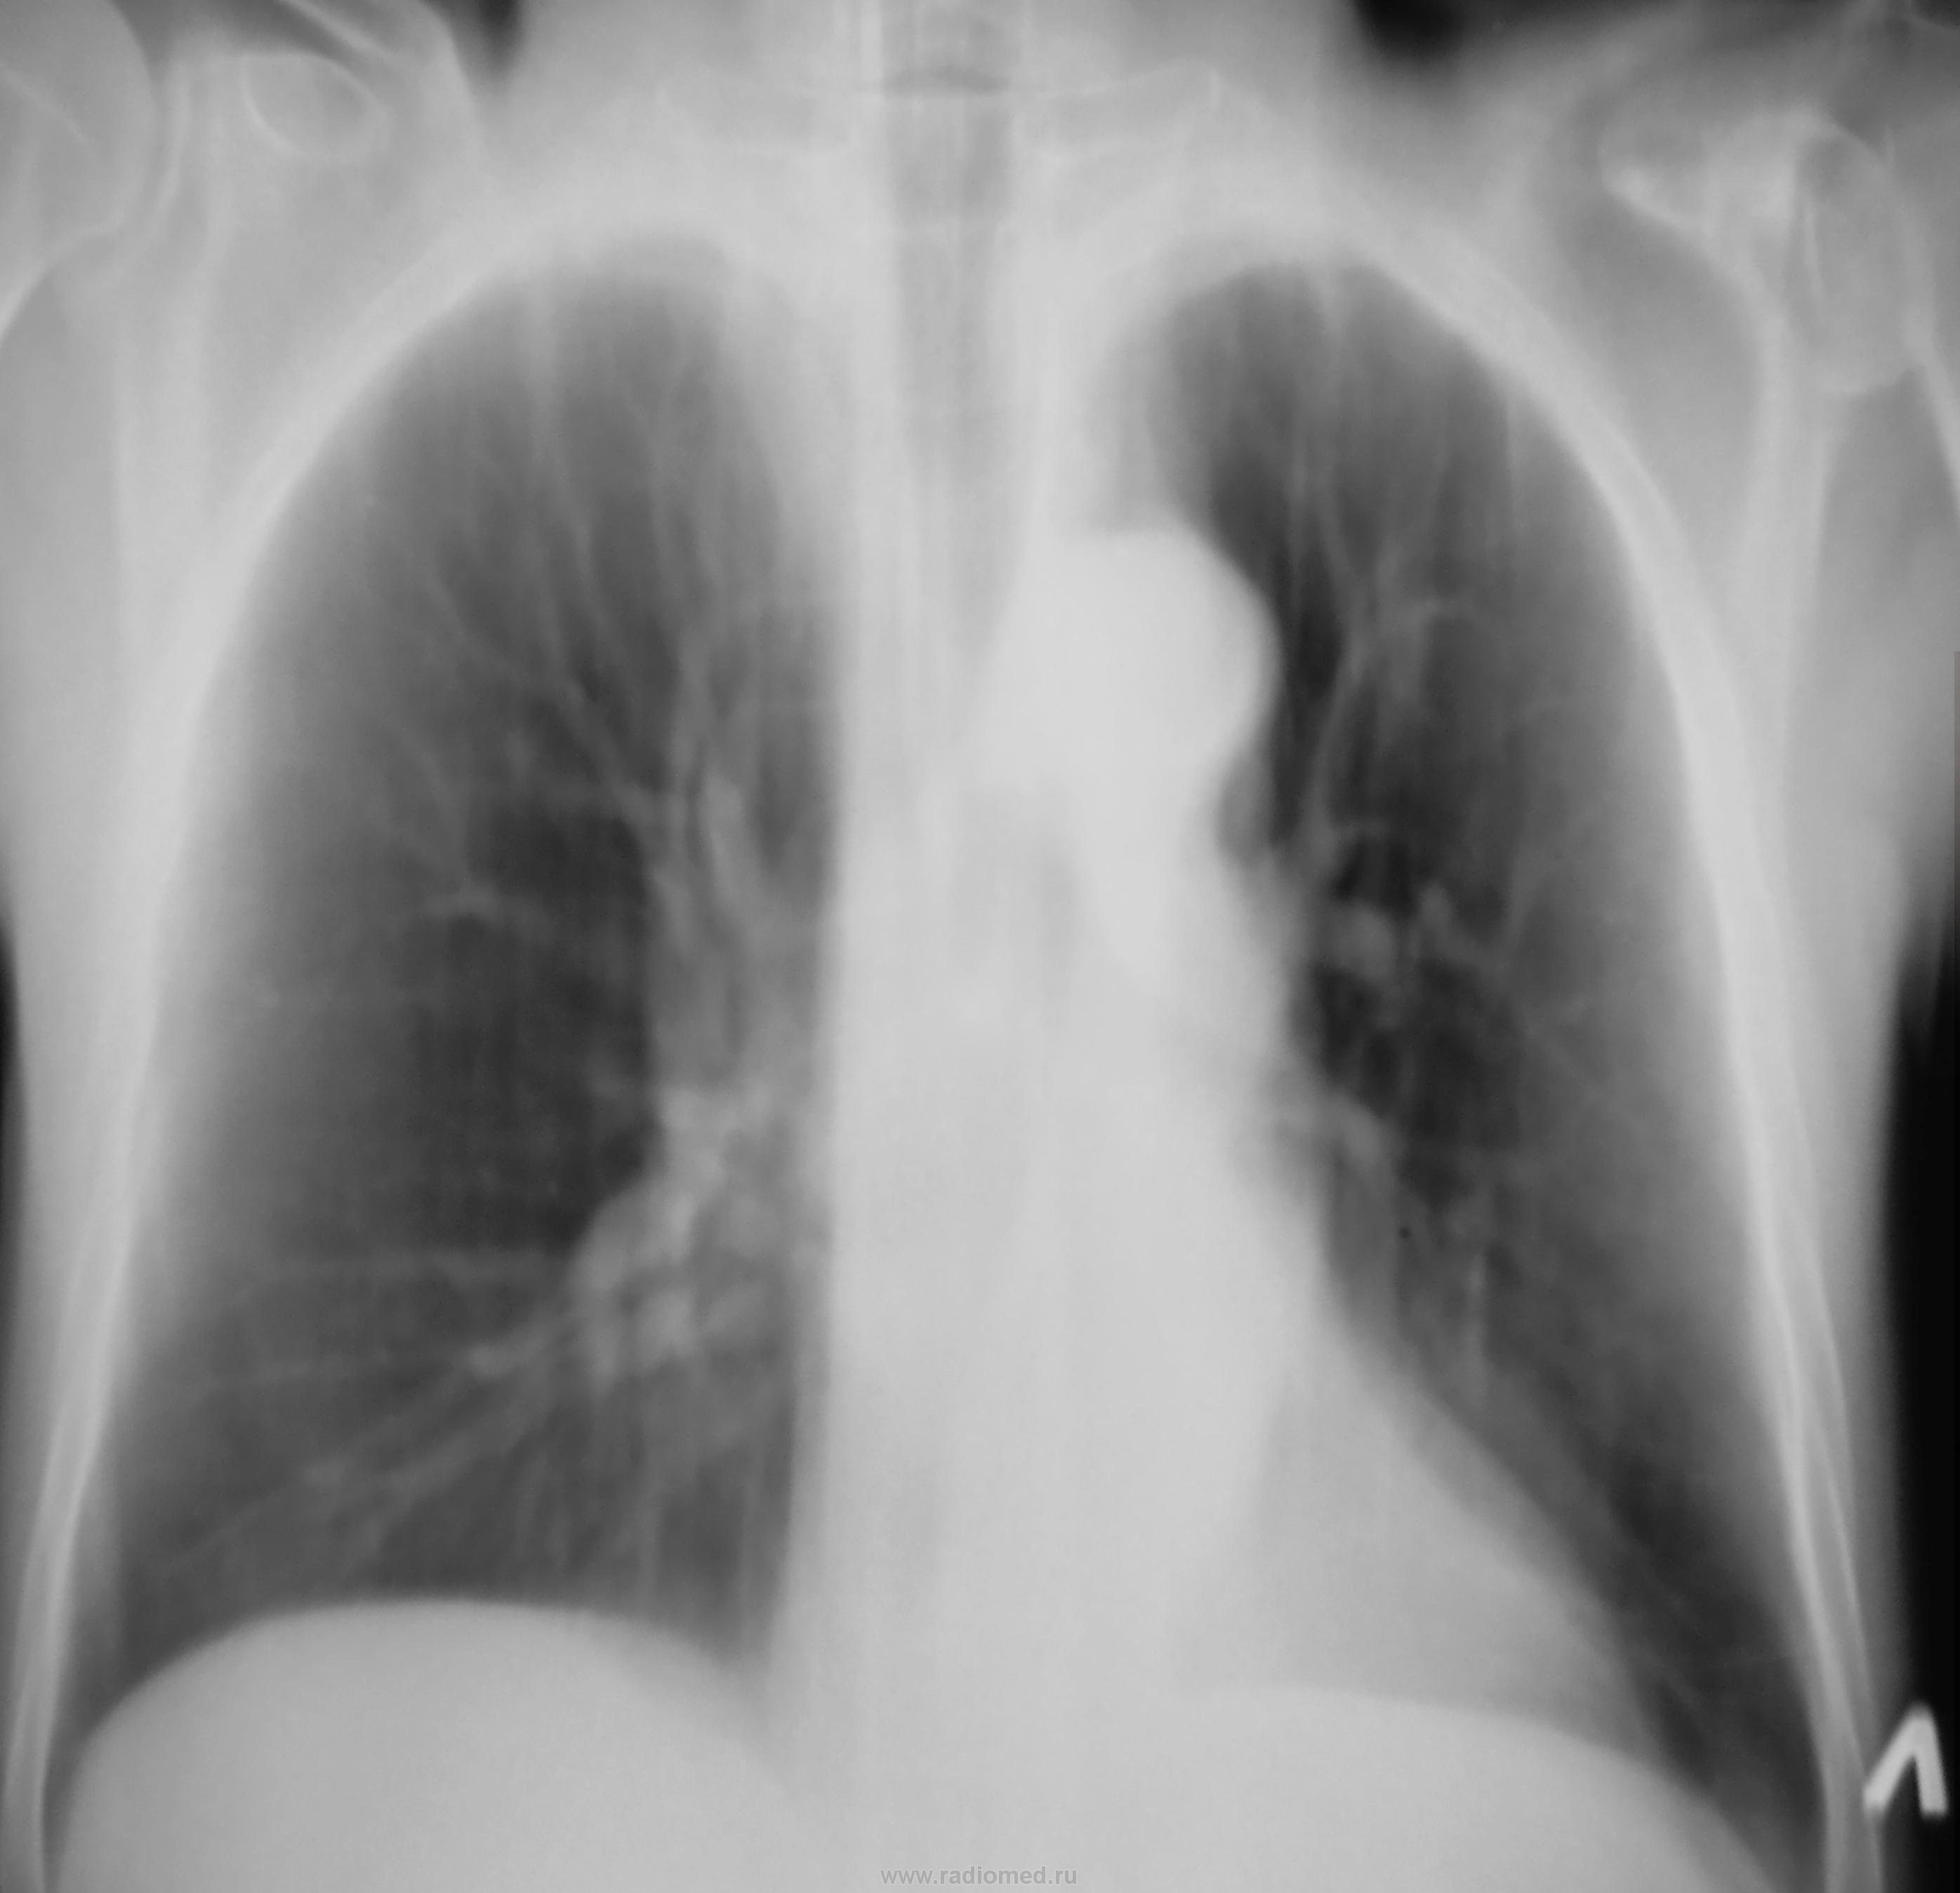

Пациент был взят после флюорографии на контроль.

Какие мнения будут уважаемые коллеги?

В 2-ке слева участок фиброза или чего-то хуже. В средостении ничего не видно, аорта искривлена. Надо делать желудок и смотреть.

Есть объёмное уменьшение левого лёгкого?

т.к. левая и правая половины диафрагмы находятся на одинаковом уровне, имеется смещение тени средостения влево, необычное положение азиго-пищеводной тени, повышение прозрачности правого легкого. Дополнительная тень на фоне сердца. См. рисунок. Все это может указывать на ателектаз 10 сегмента нижней доли левого легкого, а может быть и более. Такое суждение можно сделать по обзорной рентгенограмме в прямой проекции. Нужна левая боковая рентгенограмма.